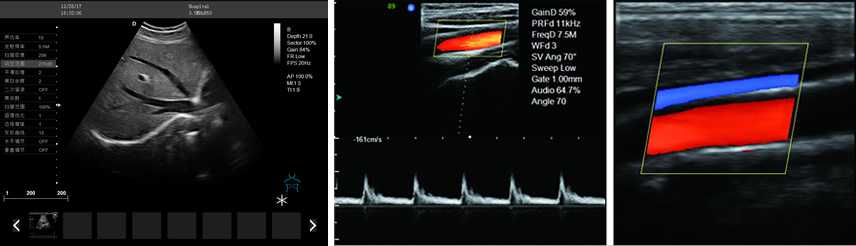

DW-PF522全數字彩色多普勒超聲診斷儀

彩色多普勒

產品性能:高集成數字式彩色多普勒技術,寬頻探頭,強勁的組合式模塊化軟件設計,全數字式大容量圖像存貯和文件歸檔管理,適用范圍:用于人體超聲診斷檢查。